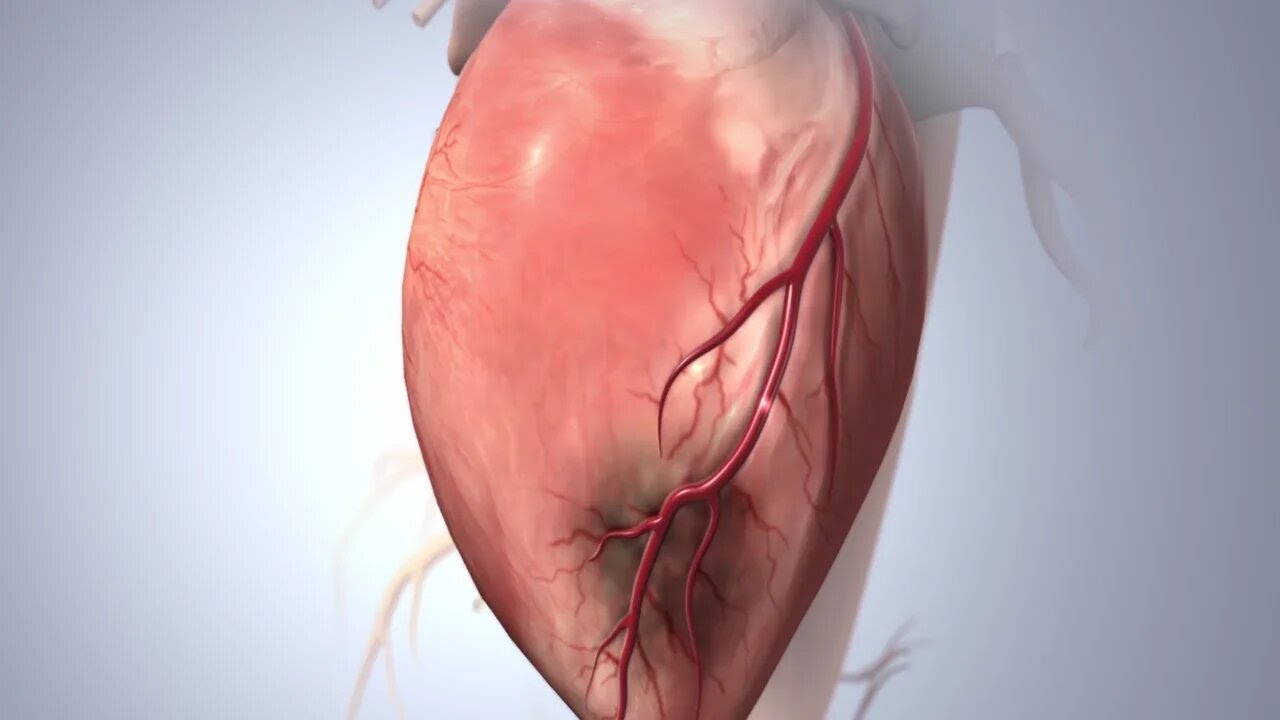

-Kalp damarlarının görüntülenmesi (Anjiyo; koroner anjiyografi)

-Kalp damarlarındaki darlık ve tıkanıklarının stent ile ameliyatsız açılması [Kronik tam tıkanıklıklar (CTO), LMCA, Rotapro, IVL ve çatallı damarlar (bifurkasyonlar) dahil tüm kompleks stentleme işlemleri]

- Miyokard Enfarktüsü (Kalp Krizi)

- Koroner Arter Hastalığı